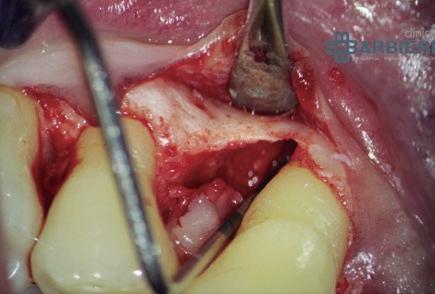

2.5. Lesión endo-periodontal

El diagnóstico, como para cualquier patología, resulta fundamental e imprescindible. Si estamos ante una lesión endo-periodontal y tratamos solo la parte periodontal o endodóntica, el fracaso estará asegurado. El tratamiento en este tipo de lesiones deberá ser combinado. Hay profesionales que abogan por comenzar primero por el tratamiento endodóntico mientras que otros prefieren empezar por el periodontal. En mi opinión, si la lesión tiene un componente combinado, habrá que hacer ambos tratamientos con el menor tiempo posible entre uno y otro, sin importar el orden de las intervenciones. Dependiendo de la situación clínica, habrá algún caso que pueda ser conveniente empezar por uno u otro procedimiento. Por ejemplo, si creemos que será un diente que acabe con una cirugía periapical, lógicamente es preferible empezar por el tratamiento endodóntico. Idealmente, obturar los últimos milímetros del conducto (o conductos) con un material biocompatible (por ejemplo, MTA) que permita hacer una pequeña apicectomía y regeneración periodontal al mismo tiempo (caso 2) y, de esta manera, hacer al paciente una única intervención quirúrgica. También podríamos estar ante un caso en el que el tratamiento endodóntico pareciera más complejo que el periodontal/quirúrgico, pudiendo ser preferible empezar por el endodóntico por si resulta ser imposible su tratamiento y, de esta forma, le evitaríamos al paciente una cirugía innecesaria. Por el contrario, si el tratamiento periodontal es el que claramente pareciera más complejo y con riesgo de acabar en exodoncia, podría resultar más lógico empezar por la parte periodontal para evitar un tratamiento endodóntico innecesario en caso de decidir hacer la exodoncia durante el

CASO 2

procedimiento periodontal/quirúrgico. De todas formas, no hay una verdad absoluta en este tema y será decisión del clínico (o clínicos) el orden y plan de tratamiento a seguir.

Como en casi todos los aspectos de la vida, la habilidad y experiencia son un grado; al menos en la mayoría de las ocasiones. Cuando hablamos de técnicas quirúrgicas esto tiene aún más importancia. Un estudio multicéntrico de Tonetti del año 200212 representa muy bien esto que comento. Ocho expertos de diferentes universidades comparan los resultados entre cirugías de acceso frente a técnicas de regeneración periodontal aplicando proteínas derivadas de la matriz del esmalte. Curiosamente, los datos obtenidos mostraron cuatro veces mejores resultados en-

SLesión endo-periodontal tratada previamente mediante endodoncia y, posteriormente, cirugía periapical con apicectomía y regeneración periodontal aplicando proteínas derivadas de la matriz del esmalte.